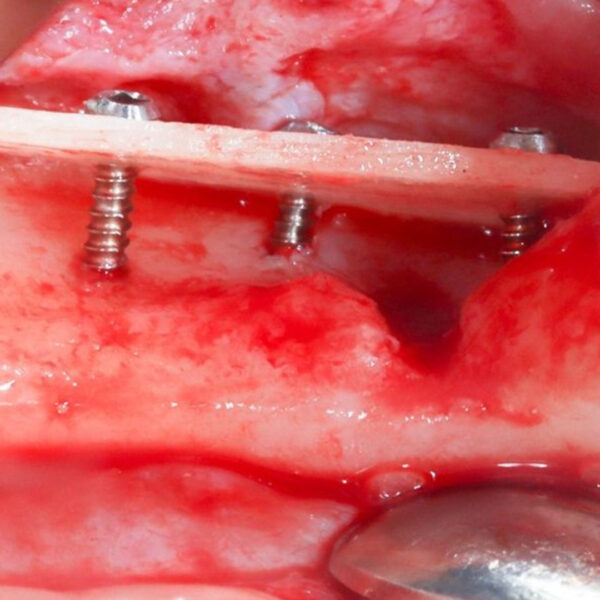

High Quality Surgical Recordings

Study high-quality surgical recordings that capture procedures step-by-step, allowing you to observe critical decision-making, tissue handling, and anatomical management in real clinical scenarios.

- Khoury | Shell Technique Using Allogenic Shell Plates (Hands On)